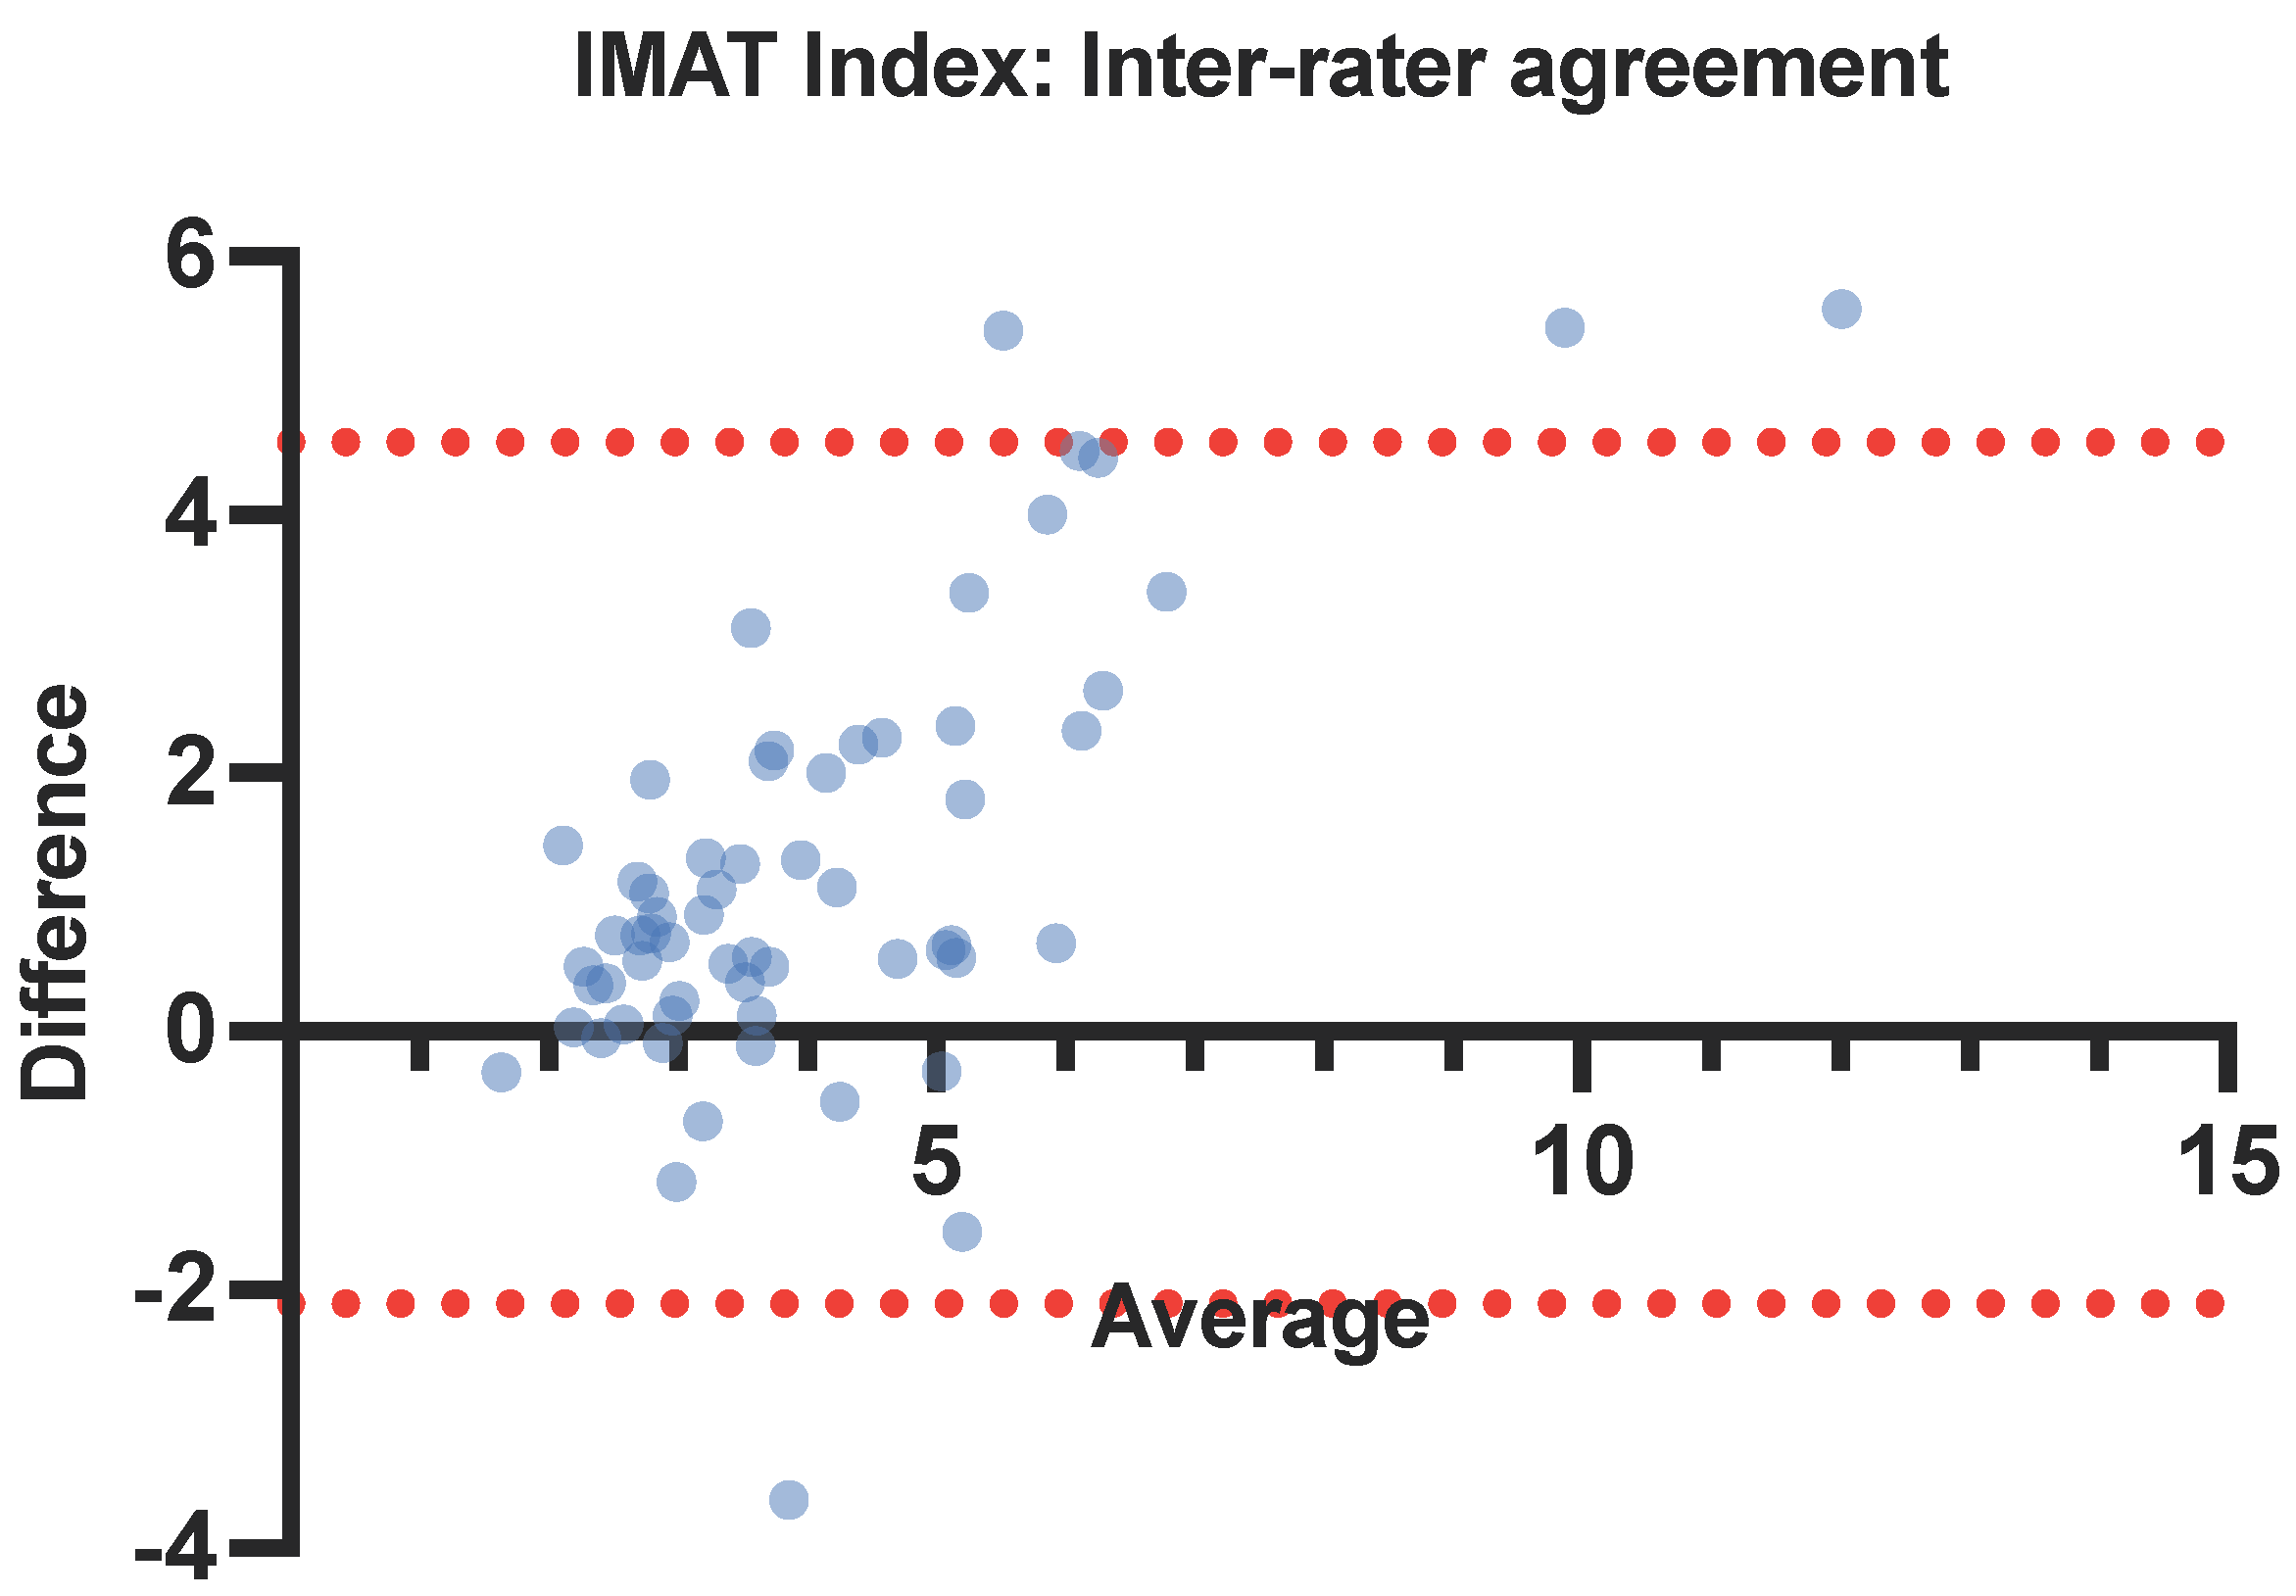

3.3. Intra- and Inter-Rater Reliability

4.2. Reliable—Inter-Rater Variability

| Muscle Parameter | Inter-Rater Reliability | ||||

|---|---|---|---|---|---|

| User 1 | User 2 | ICC | 95% CI | p-Value | |

| RF IMAT (%) | 14.3 (3.22) | 15.1 (3.12) | 0.631 | 0.377–0.77 | <0.001 * |

| RF IMAT index (%/cm2) | 4.7 (2.44) | 3.48 (1.4) | 0.776 | 0.284–0.852 | <0.001 * |